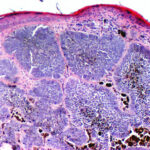

PIGMENTED BASAL CELL CARCINOMA

Pigmented BCC is a sub-type of nodular BCC that exhibits increased melanization. Pigmented BCC appears as a hyperpigmented, translucent papule, which may also be eroded (Fig. 115-3). The differential diagnosis includes nodular melanoma.

Pigmented Basal Cell Carcinoma

Pigmented BCC shows histologic features similar to those of nodular BCC but with the addition of melanin.38 Approximately 75 percent of BCCs contain melanocytes, but only 25 percent contain large amounts of melanin. The melanocytes are interspersed between tumor cells and contain numerous melanin granules in their cytoplasm and dendrites. Although the tumor cells contain little melanin, numerous melanophages populate the stroma surrounding the tumor.